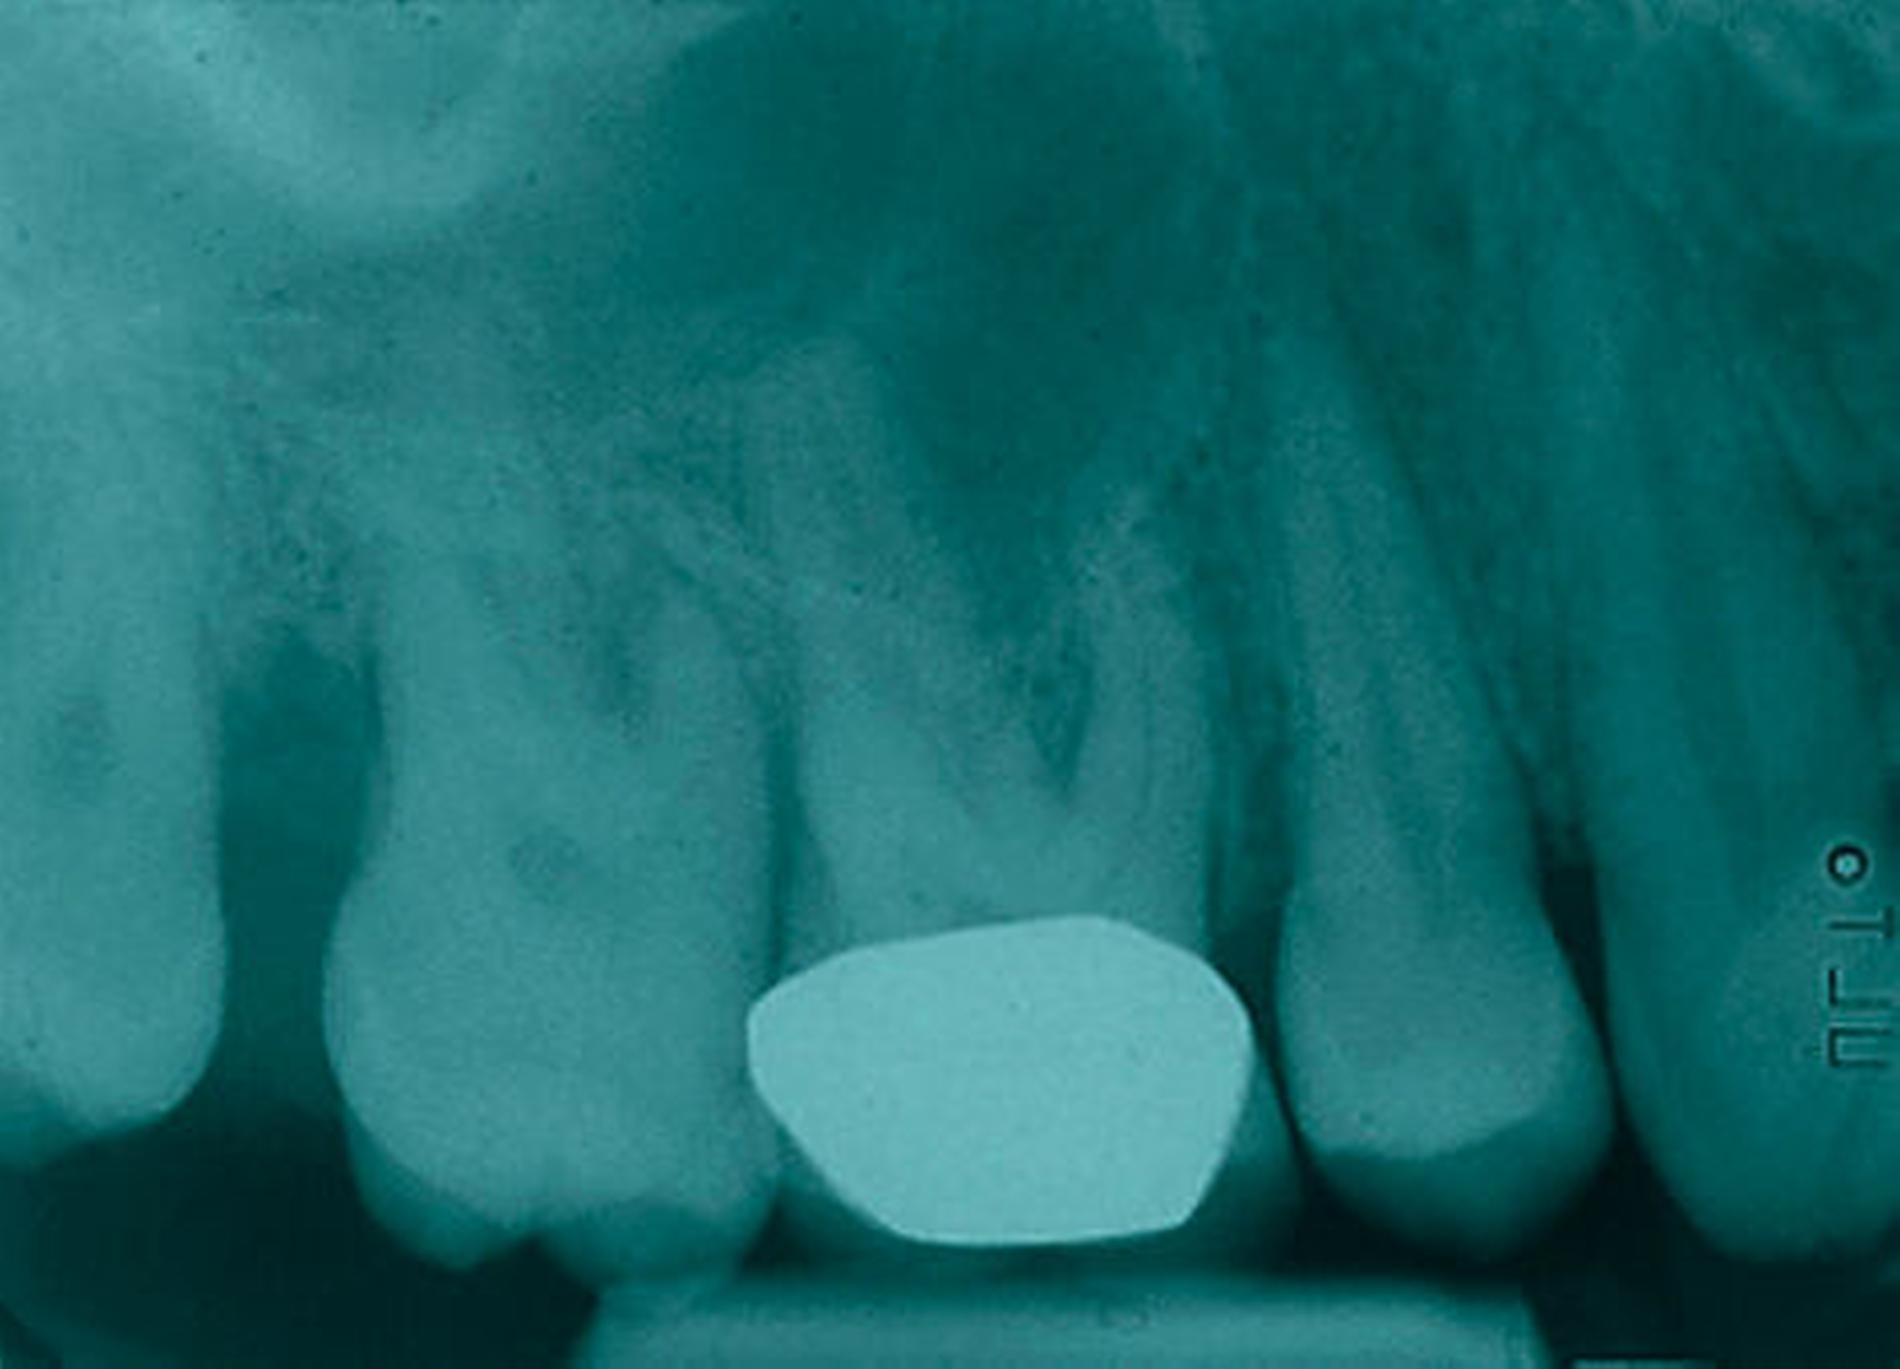

Am 27.07.2007 wurde ein Kontroll-Röntgenstatus in Rechtwinkel-Parallel-Technik bestehend aus zehn Einzelzahnfilmen erstellt. Folgende Unterschiede zum Anfangsstatus lassen sich feststellen: Es zeigte sich eine generalisierte Restitution der Lamina dura des Limbus alveolaris, insbesondere in den Regionen 16 und 17 mesial und distal, 26 mesial, 27 distal, 36 distal, 37 mesial, 46 distal, 47 mesial. Die Parodontalspalten der Zähne 17, 26, 27 erscheinen nicht mehr erweitert. Bei den Zähnen 16 mesial, 17 und 27 distal, 37 distal, 46 distal und 47 mesial zeigt sich eine partielle knöcherne Auffüllung der vertikalen Defekte. Die in Abbildung 9 (OPG von 2011) dargestellte Knochenlinie zeigt im Vergleich zu den Vorbefunden kaum Veränderungen.